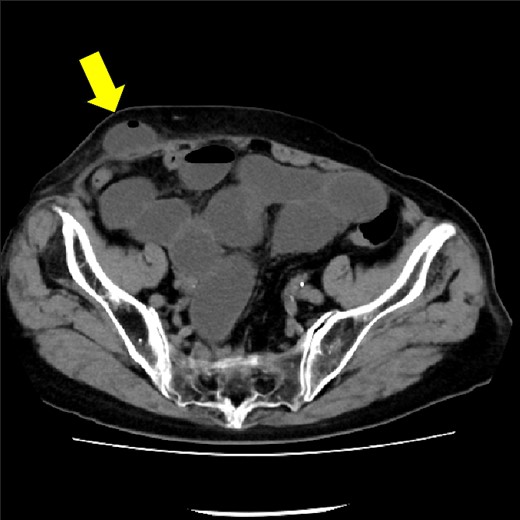

The drain was removed on postoperative day 2. On the night of the third postoperative day, the patient vomited. On the morning of the fourth postoperative day, mild abdominal pain and a ping-pong ball-sized bulge and induration were found near the surgical scar of the 5 mm port where the drain had been placed. CT confirmed an incarcerated small intestine and ileus in the 5 mm port scar where the drain had been placed (Fig. 2). Ileus removal was performed on the same day. First, the dilated wound for nephrectomy was opened, and the inside of the abdominal cavity was observed. A hanging small intestine was observed just below the 5 mm port (Fig. 3). Since it could not be conquered manually, a 2 cm vertical incision was made on the 5 mm port wound. The small intestine penetrated the anterior layer of the rectus abdominis muscle, so the fascia was carefully incised to avoid damaging the small intestine. The small intestine was returned to the abdominal cavity. The small intestine was slightly discolored (Fig. 4), but after discussion with the gastrointestinal surgeon, it was determined that it was not necrotic. No small intestine resection was performed. The wound was carefully closed using fascial sutures to prevent recurrence. The fascia was weak, likely because this patient was taking steroids. The ileus has not recurred since then. The pathological results indicated a maximum diameter of 30 mm, consistent with papillary renal cell carcinoma, classified as pT1a G3 > G2, with negative margins.

CT showing small intestine penetrating fascia of rectus abdominis. The arrow shows the incarcerated small intestine.